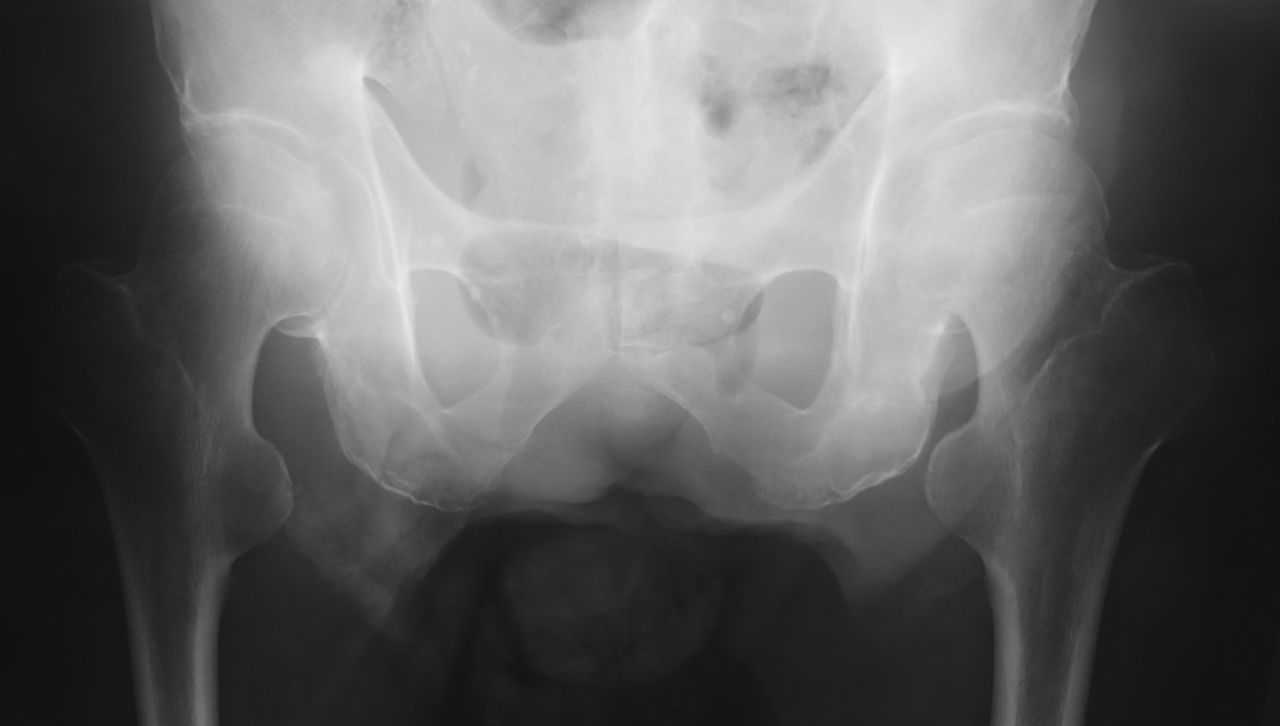

CTでは左腎背側に筋欠損部が存在し、そこから筋層外に腎周囲の脂肪織と思われるlow density massの脱出を認めではないですか!

おかしいなぁ と思いながらも脂肪腫ならば、とMRIを依頼しました。しかし、MRIの画像を確認すると明らかに背筋が欠損しており、腫瘤は後腹膜の脂肪組織と連続していました。

外科医師に相談すると、これは特発性の「上腰ヘルニア」ではないかとのことでした。患者さんの腰背部腫瘤を触知すると、患者さんの発声が腫瘤を通じてダイレクトに私の手に伝わります。